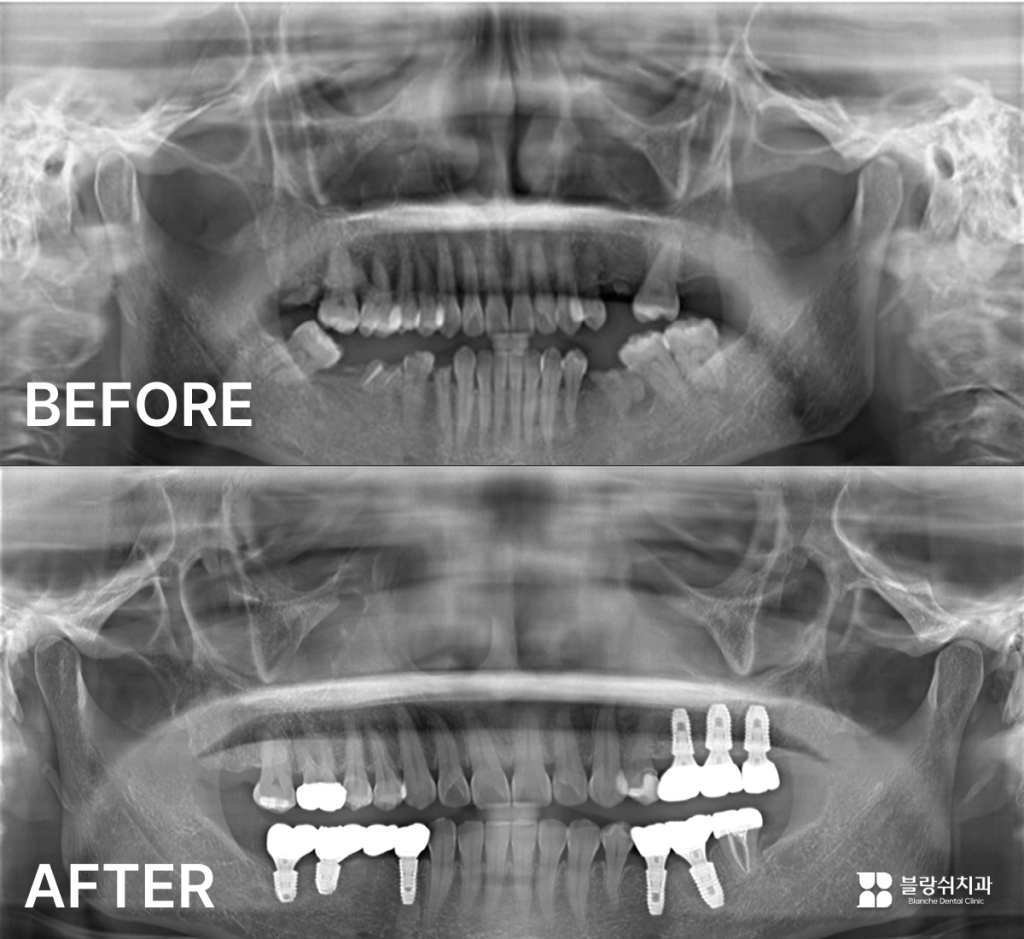

- 상황 치과공포증으로 오랫동안 치료를 미룬 환자분이었습니다. 그 사이 충치와 치관 파절, 치아 상실, 잇몸 염증까지 복합적인 문제가 진행된 상태였고, 총 8개의 임플란트가 필요했습니다.

- 치료방법 두려움이 큰 만큼 수면 임플란트(의식하 진정)로 진행했습니다. 진정 상태에서 임플란트 8개 식립과 신경치료, 크라운 치료까지 한 번에 마무리했습니다.

- 결과 한 번의 수술로 전체 치료를 완료했습니다. 치료 후 환자분은 자연스럽게 깨어났고, “진작 올 걸 그랬다”며 높은 만족감을 표현하셨습니다.

- 수면 임플란트가 도움이 된 이유 치과공포증이 있는 환자에게 수면 임플란트는 긴 수술 시간을 두려움 없이 견딜 수 있게 해줍니다. 또한 여러 치료를 한 번에 묶어 진행할 수 있어 내원 횟수도 줄일 수 있습니다.